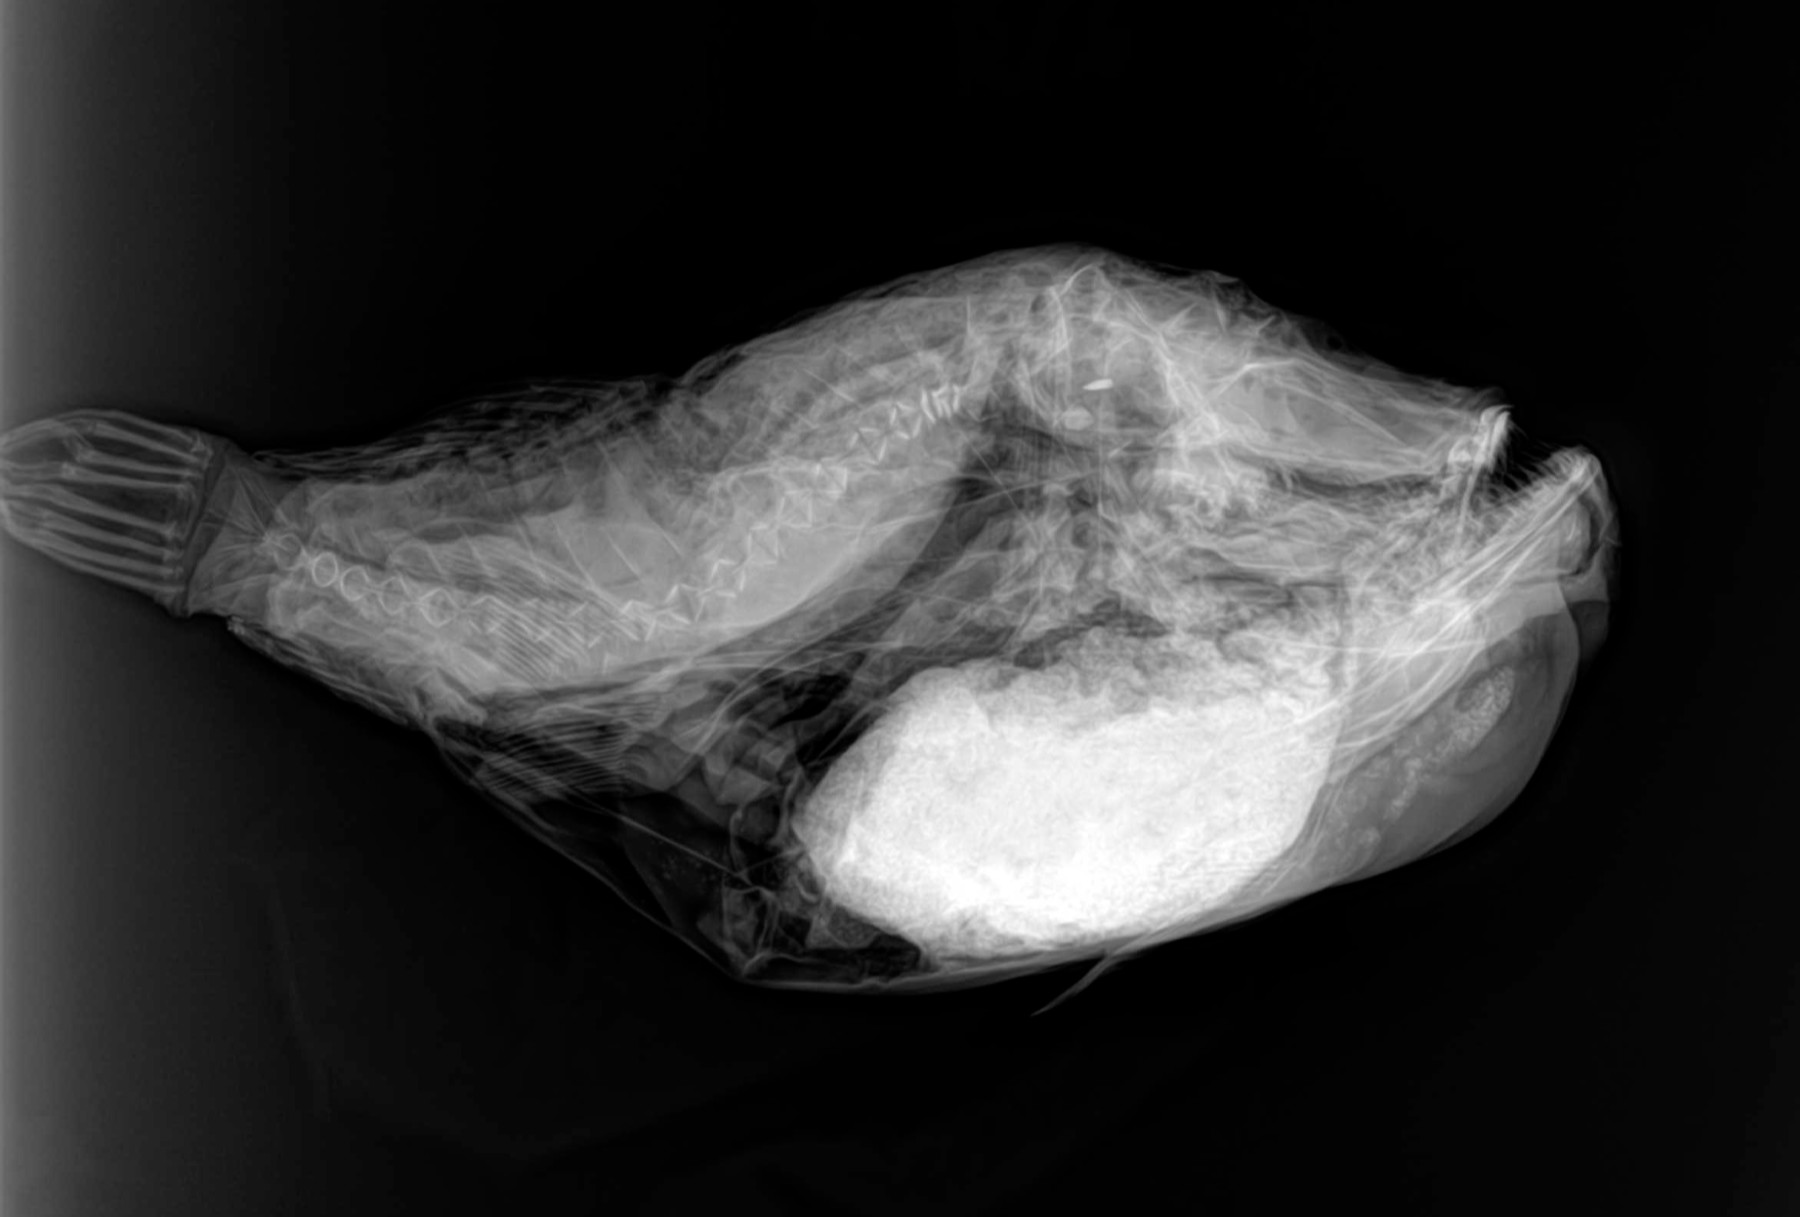

Radiología Digital como Herramienta Complementaria en el Dictamen de Bienes Muebles

Desde el descubrimiento de los rayos “X” y las placas radiográficas por Wilhelm Conrad Roentgen y su posterior difusión a través de la Asociación Físico médica de Wurzburg el 28 de diciembre de 1895, que fue la primera asociación que habló de los nuevos rayos que podían penetrar el cuerpo y fotografiar los huesos, ha habido muchos cambios tanto en la forma de obtener, procesar e incluso en la forma de visualizar, manejar y almacenar las placas radiográficas.